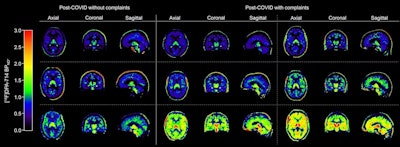

After adjusting for age, body mass index, and PET scanner type, the researchers found significantly higher binding in global gray matter in individuals with versus without persistent complaints (nondisplaceable binding potential, 0.8 ± 0.34 vs. 0.65 ± 0.17, p = 0.036). Additionally, while no significant differences in binding levels of the other regions were observed between groups, visual inspection showed similar high binding levels in the cerebellum in some with persistent complaints compared to those without complaints.

Examples of quantitative cerebral F-18 DPA-714 images of brain in post-COVID individuals. *Parametric Logan VT images corrected for K1/k2 (global cerebral region; gray and white matter) and subtracted by 1, creating indirect BPND images. VT = total distribution volume.Journal of Nuclear Medicine